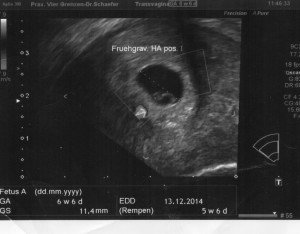

Heute gab es ein Fotoshooting der besonderen Art beim Opa auf Arbeit. Sein Kollege, der stellvertretende Chefarzt der Kinderklinik und gleichzeitig Guru des Ultraschalls, hatte sich bereit erklärt den werdenden Eltern noch ein paar aktuelle Fotos zu machen. Leider gab es kein 3D, aber dafür ein paar süße Fotos und vor allem Videos unseres Sohnemannes, der sich die ganze Zeit über ruhig verhielt und sich der Kamera, äh dem Schallkopf stellte.